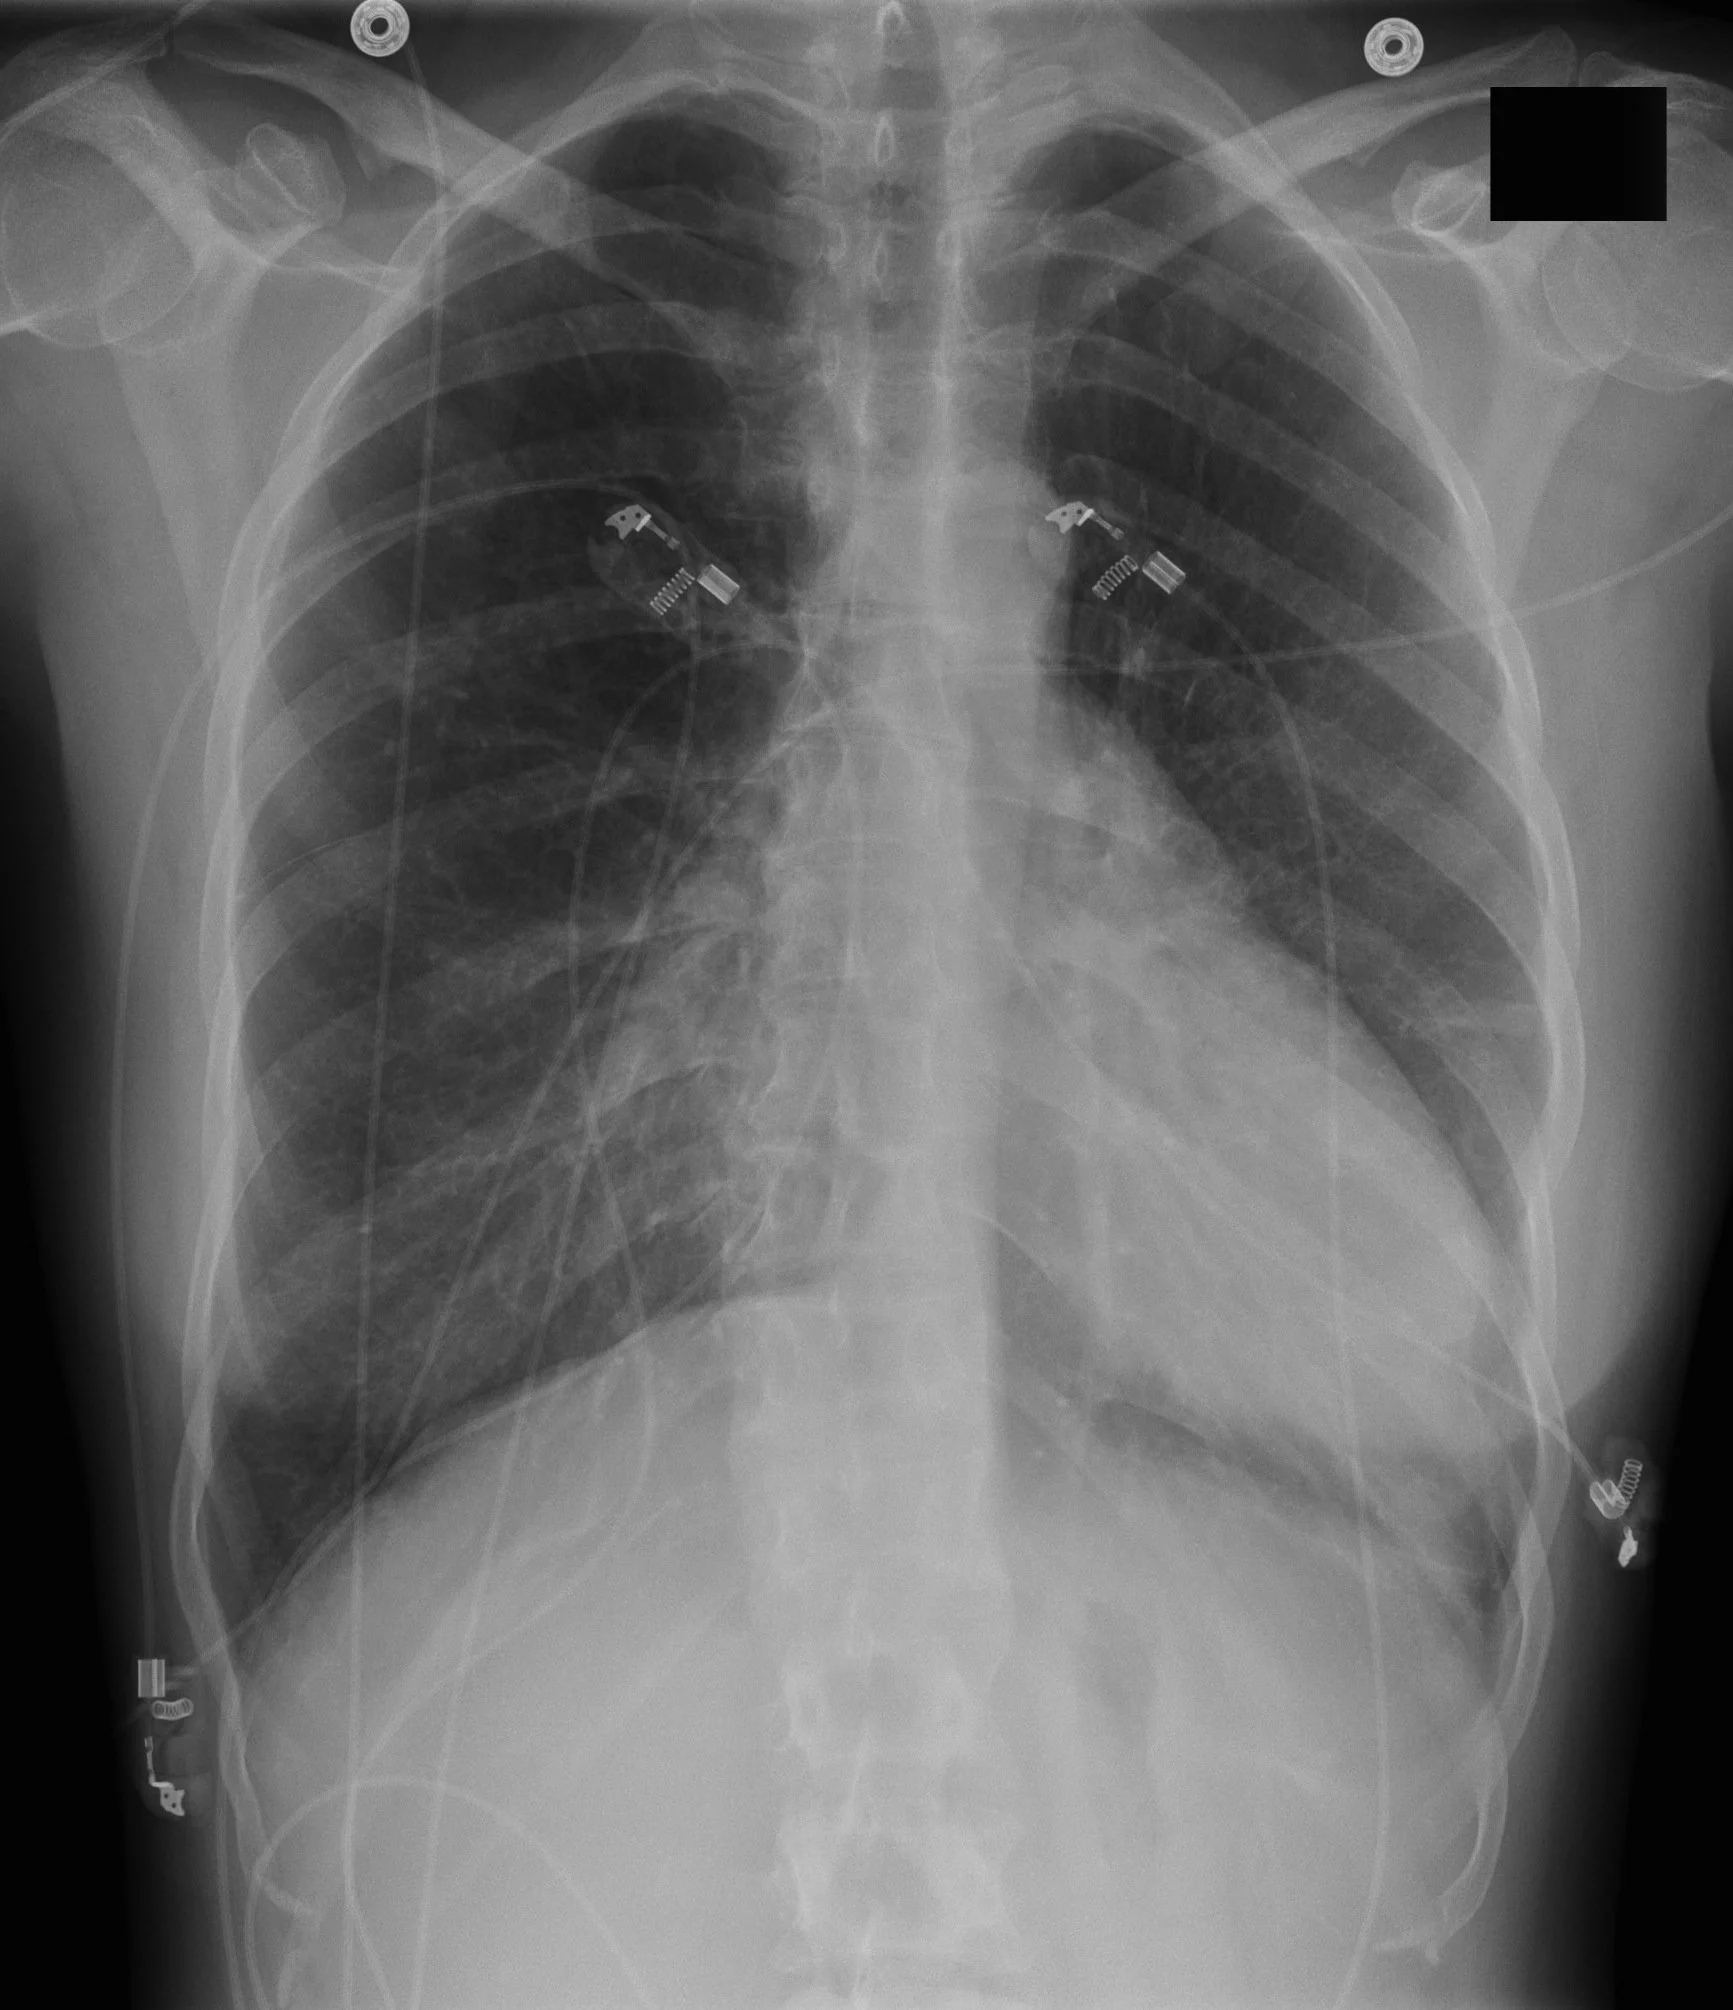

Hoffman-Rigler Sign

• Seen in LV hypertrophy

• Only seen on lateral radiograph and measured 2 cm above the intersection of IVC and diaphragm

• Distance between the LV border and posterior border of IVC is >2.8cm